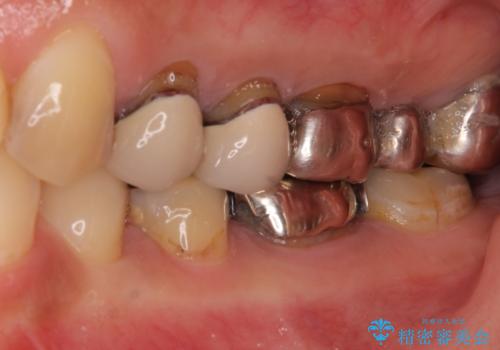

- 歯肉が退縮したためにクラウンの縁や歯根が見えてしまっていることを気にして来院された患者様です。

仮歯に変えた後にオールセラミッククラウンにて補綴することとしました。

強い咬合力や磨きすぎなどにより、歯根が見えてしまったり、金属の縁が見えてしまったりし、審美障害を引き起こすことがあります。

歯根が変色してしまうと、歯肉越しに歯根の黒い色が透けてしまうことがあり、この点についてはどうにも施しようがないため、患者様には事前のご理解いただきました。

治療前と比べてとても自然な前歯となり、患者様には大変満足していただきました。